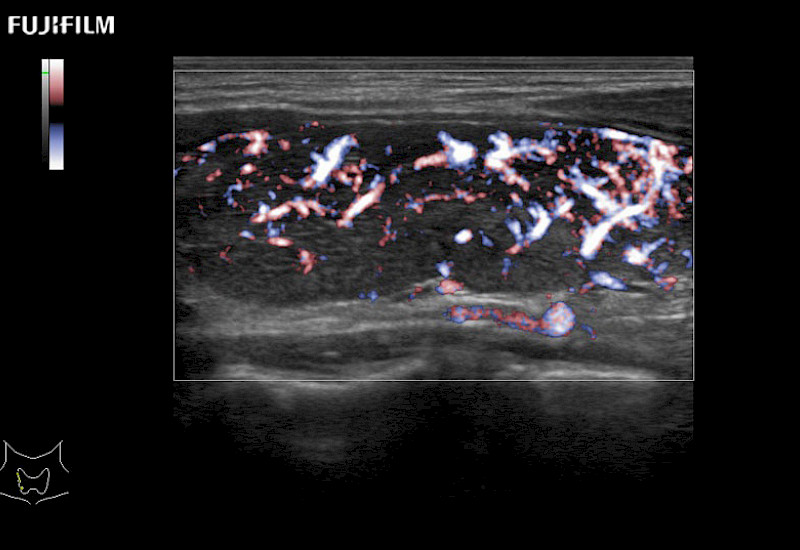

Our dedication to Surgical Oncology allows us to offer superior image quality, outstanding system reliability and intuitive use of cutting edge technology.

The ARIETTA 750 incorporates all of the proven technologies and functions that medical professionals have come to expect from Fujifilm Healthcare.

ARIETTA 750 is the definitive diagnostic ultrasound solution for any clinical setting - Private Office, Imaging Center, or Hospital. The ARIETTA platform provides the ultimate in clinical performance with its state-of-the-art features and large user-friendly display.